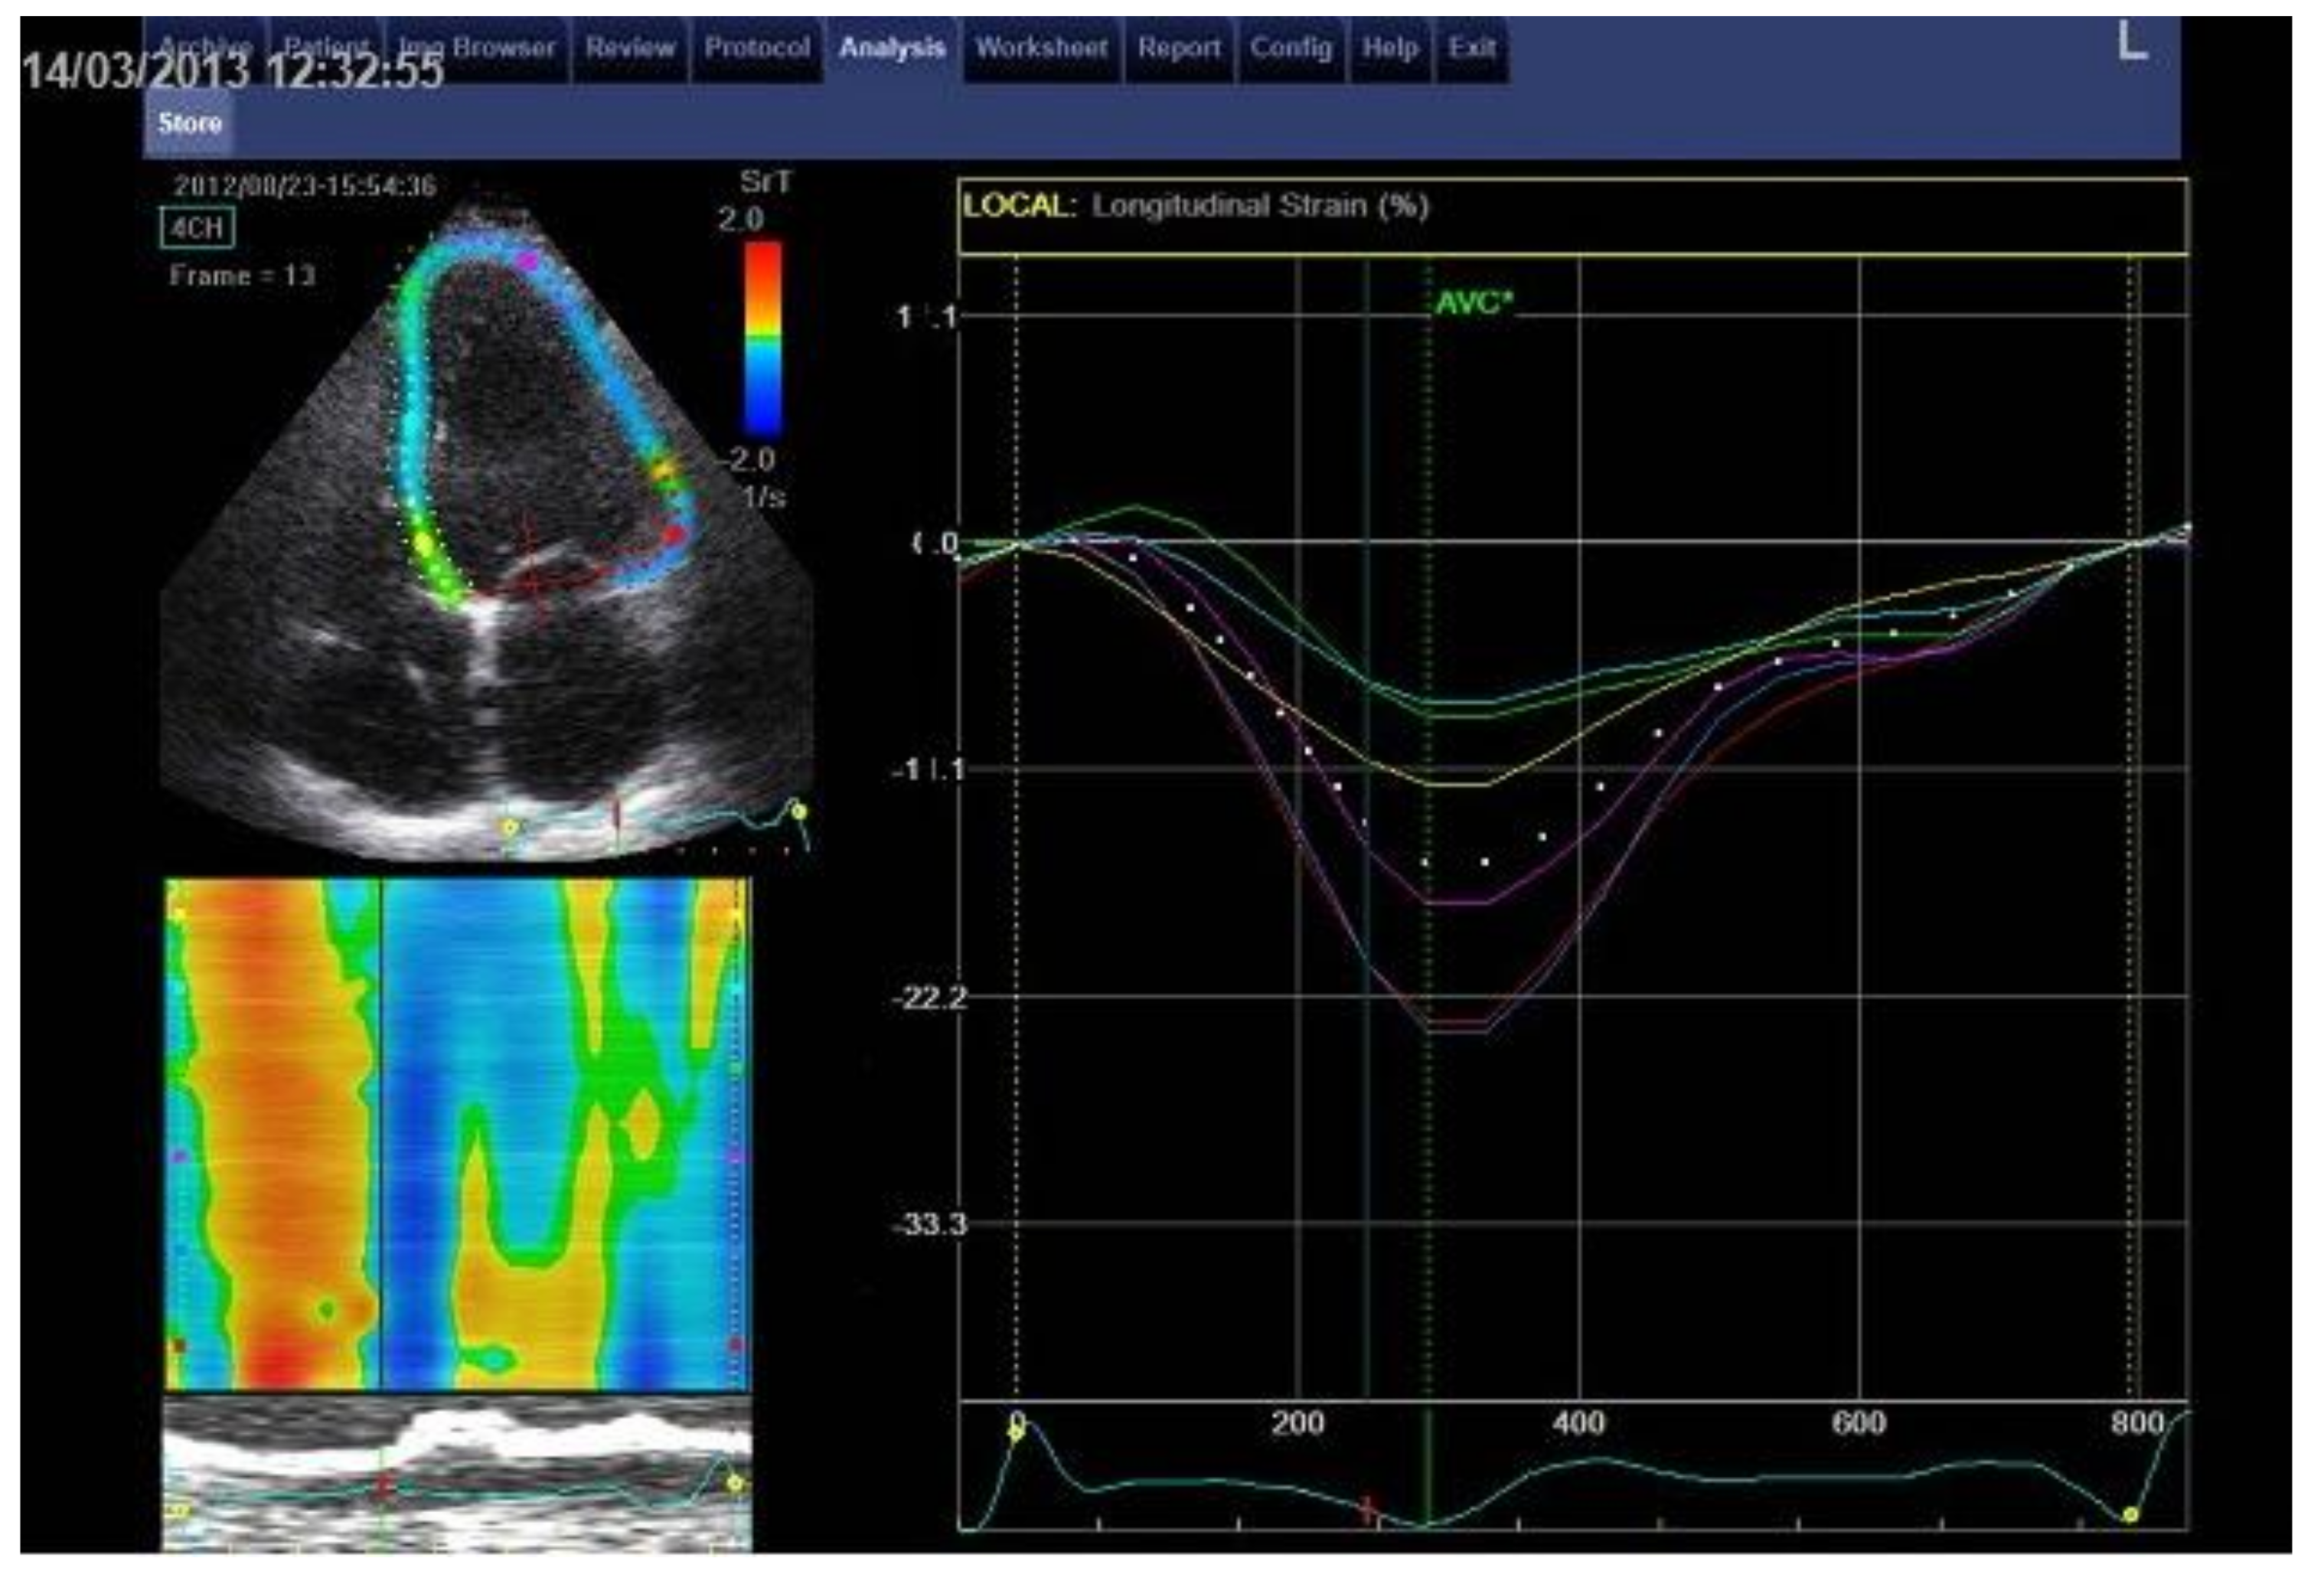

2.4. Echocardiography

2.4.2. LV Two-Dimensional Speckle-Tracking Echocardiography (STE)